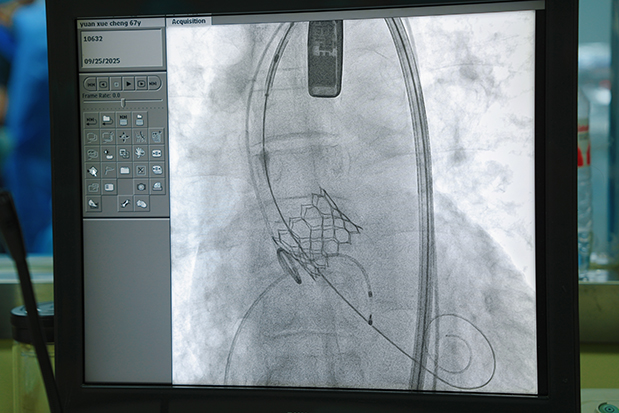

9月25日,手术团队为袁先生实施了TAVR手术。手术采用经股动脉入路,首先在患者右侧股动脉处进行穿刺,建立血管通路,随后沿导丝置入输送鞘管。将压缩状态的人工生物瓣膜装载于专用输送导管上,在数字减影血管造影(DSA)影像引导下,将输送导管精准送至主动脉瓣环水平。通过食管超声及DSA双重定位确认瓣膜位置无误后,强制高频起搏心脏、释放人工瓣膜,使其与自身主动脉瓣环紧密贴合,实现瓣膜功能重建。整个手术过程操作精准,时间短,术中生命体征平稳,有效规避了传统手术的高风险因素。

多学科协作保成功,术后恢复超预期

本次TAVR手术的成功实施,得益于该院多学科团队的紧密协作与高效配合。术中,麻醉科团队负责实施麻醉、维持呼吸循环稳定及术中用药调控,超声科团队通过经食管超声实时评估瓣膜位置、形态及功能,手术护理团队保障手术器械及耗材配合使用,心内科团队做好冠脉保护应急保障,各环节衔接有序,为手术安全提供了坚实保障。当人工瓣膜释放完毕后,经食管超声即时评估显示:人工瓣膜位置满意,瓣口血流通畅,无明显瓣周漏,跨瓣压差恢复正常,患者心脏血流动力学指标较术前显著改善,手术取得圆满成功。